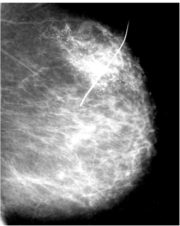

| 09:51, 7 בספטמבר 2012 | Coreneedle2712.png (קובץ) |  |

142 קילו־בייטים | Motyk | 1 | |